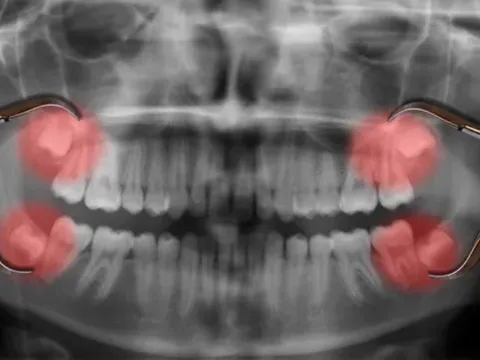

Tại sao răng khôn lại mọc muộn?

DNVN - Việc nhổ răng khôn từ lâu đã trở thành “nghi thức trưởng thành” quen thuộc của nhiều người. Nhưng một câu hỏi lớn đặt ra: Tại sao những chiếc răng này lại mọc muộn đến vậy, thay vì xuất hiện cùng các răng vĩnh viễn khác khi còn nhỏ?